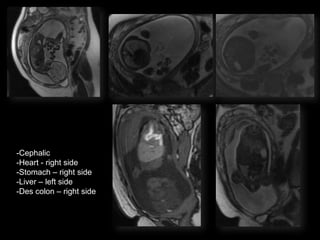

POSTNATAL BABYGRAM

-Cephalic

-Heart - right side

-Stomach โ€“ right side

-Liver โ€“ left side

-Des colon โ€“ right side

Situs Inversus Totalis

โ€ข 3-5% with cardiac abnormalities

โ€ข 25% with primary ciliary dyskinesia (PCD)

โ€“ Kartagenerโ€Ÿs Syndrome

โ€“ Chronic sinus infections; respiratory infections;

infertility

Terminology

โ€ข Situs solitus โ€“ normal anatomy

โ€ข Situs inversus โ€“ mirror image of normal

โ€ข Situs ambiguous โ€“ heterotaxy

โ€“ Disordered arrangement of organs in chest and

abdomen

โ€“ Asplenia โ€“ right atrial isomerism

โ€“ Polyslenia โ€“ left atrial isomerism

Esophageal Atresia

โ€ข Polyhydramnios

โ€ข small / absent stomach if no

fistula

โ€ข Often other assoc anomalies

โ€“   Imperforate anus

โ€“   Duodenal atresia/stenosis

โ€“   Vertebral/rib anomalies

โ€“   VACTERL spectrum